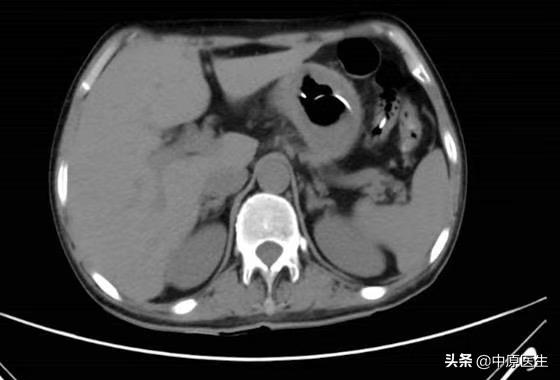

经过思考,我们认为可能与下列因素有关:1、因为是突然出现,是不是空肠营养管脱出?或者是空肠远端梗阻?立即完善胃镜及腹部CT检查,结果未发现空肠营养管脱出,也未发现明显的梗阻;2、难道是导管发生了破损,导致营养液漏到胃内?向空肠营养管内输注少量亚甲蓝,减压管内也引流出了蓝色液体,进一步完善小肠造影,结果回示:营养管瘘,同时也未发现肠道远端梗阻;根据这样的检查结果,我们考虑胃空肠营养减压一体管破损,于是立即行经胃镜给予更换管路。